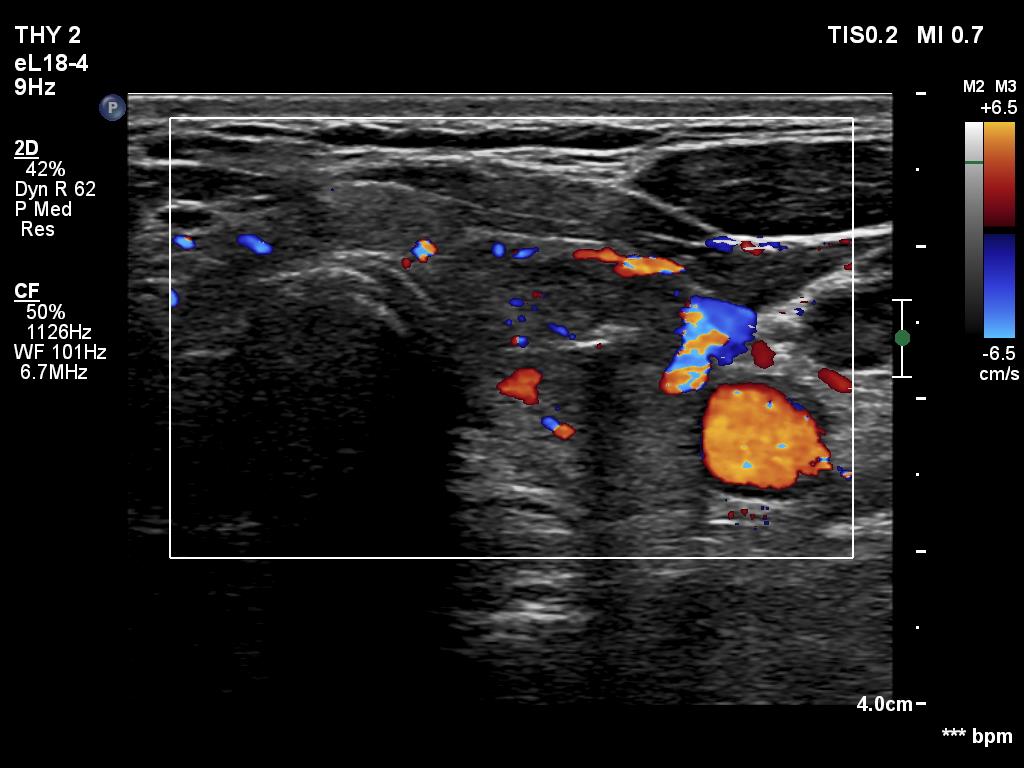

Ultrasonography. The thyroid was echonormal and had multiple minimally/moderately hypoechoic nodules. The lesion in the left lobe was remarkable due to lobulated margins. More than 10 lymph nodes larger than 1 cm in diameter were detected both in the right and the left side of the neck. Some had heterogenous pattern, most of them lacked regular hilum. The vascularity was varied from avascular to obviously irregular.